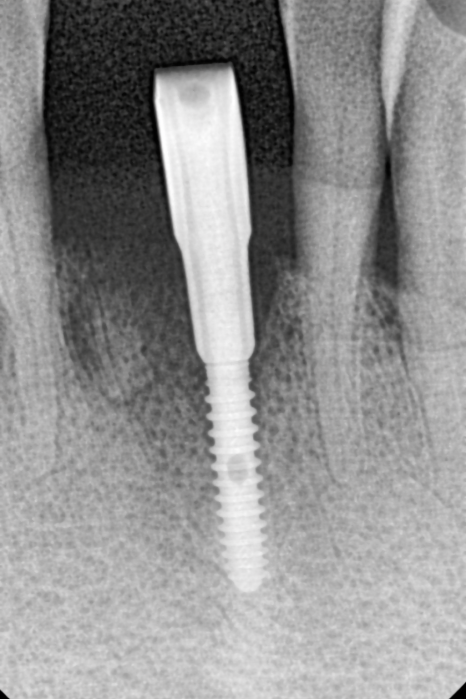

임플란트 1개로 2개를 버틴다면, 지지대는 더 든든해야 합니다.

강동구 임플란트 가격 줄이는 방법

다만 여기서 중요한

포인트가 있습니다.

임플란트를 1개만 심고

크라운을 2개로 연결하는 구조라면,

말 그대로 임플란트 뿌리(픽스처) 1개가

보철 2개를 지지해야 합니다.

그래서 이번 케이스는

일반적인 앞니용처럼

얇은 직경의 픽스처를 쓰기보다는,

직경이 더 큰 임플란트를 사용

가능한 범위 안에서

조금 더 직경이 넓은 픽스처로

계획해 안정성을 확보했습니다.

'개수는 줄이되, 지지대는 더 든든하게'

이런 방향으로 이해하시면 됩니다. ^^